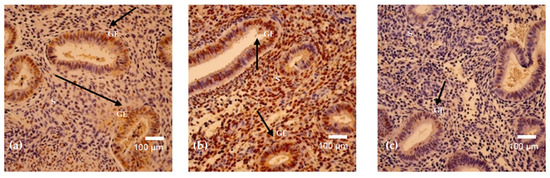

In this research, we sought to methodically examine the protective effects of Gastrodia elata extract (GEE) on liver damage induced by D-galactose (D-gal) in mice and clarify the underlying mechanisms. The chemical composition of GEE was characterized using Ultra-Performance Liquid Chromatography–Tandem Mass Spectrometry

In this research, we sought to methodically examine the protective effects of Gastrodia elata extract (GEE) on liver damage induced by D-galactose (D-gal) in mice and clarify the underlying mechanisms. The chemical composition of GEE was characterized using Ultra-Performance Liquid Chromatography–Tandem Mass Spectrometry (UPLC-MS/MS), while network pharmacology analysis was employed to predict potential molecular targets and signaling pathways. A mouse model of liver injury was established through daily intraperitoneal injection of D-gal over a 42-day period, during which the hepatoprotective efficacy of GEE was evaluated. Biochemical, histopathological, and molecular analyses were subsequently performed. UPLC-MS/MS identified ingredients such as amino acids, aromatic compounds, fatty acids, and terpenoids in GEE. A network pharmacology analysis enabled the identification of 272 common targets linked to GEE and liver damage, demonstrating notable enrichment within the phosphatidylinositol 3-kinase/protein kinase B (PI3K/Akt) signaling pathway. In vivo experiments demonstrated that GEE effectively alleviated D-gal-induced body weight loss and elevated liver index values, alleviated hepatic histological damage, and reduced serum levels of Alanine Aminotransferase (ALT), Aspartate Aminotransferase (AST), and Alkaline Phosphatase (ALP). Furthermore, GEE enhanced the activities of the antioxidant enzymes superoxide dismutase (SOD) and catalase (CAT), decreased malondialdehyde (MDA) levels, and downregulated the mRNA expression of the pro-inflammatory cytokines Interleukin-6 (IL-6), Interleukin-1 beta (IL-1β), and Tumor Necrosis Factor-alpha (TNF-α). Western blot analysis confirmed that GEE activated the PI3K/Akt pathway, as evidenced by increased ratios of phosphorylated Phosphatidylinositol 3-kinase/Phosphatidylinositol 3-kinase (p-PI3K/PI3K) and phosphorylated AKT/Protein Kinase B (p-AKT/AKT); restored the B-cell lymphoma 2-associated X protein/B-cell lymphoma-2 (Bax/Bcl-2) balance; and reduced cyclin-dependent kinase inhibitor 1 (p21) expression. The results suggest that GEE protects against D-gal-induced liver damage by reducing oxidative stress, inhibiting inflammatory responses, and modulating apoptosis through the activation of the PI3K/Akt signaling pathway, providing support for its potential use in hepatoprotection.